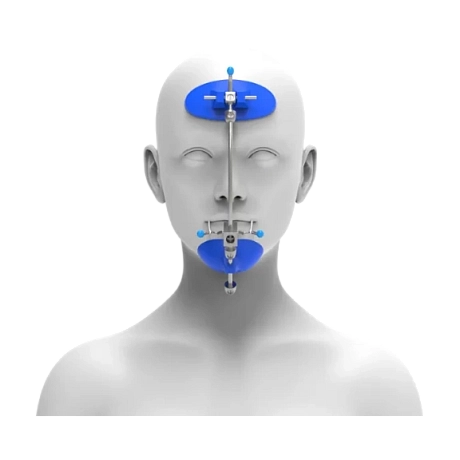

Корректор класса II Вильямса (исполнение 3) - Набор 320-0100

Описание товара

Характеристики